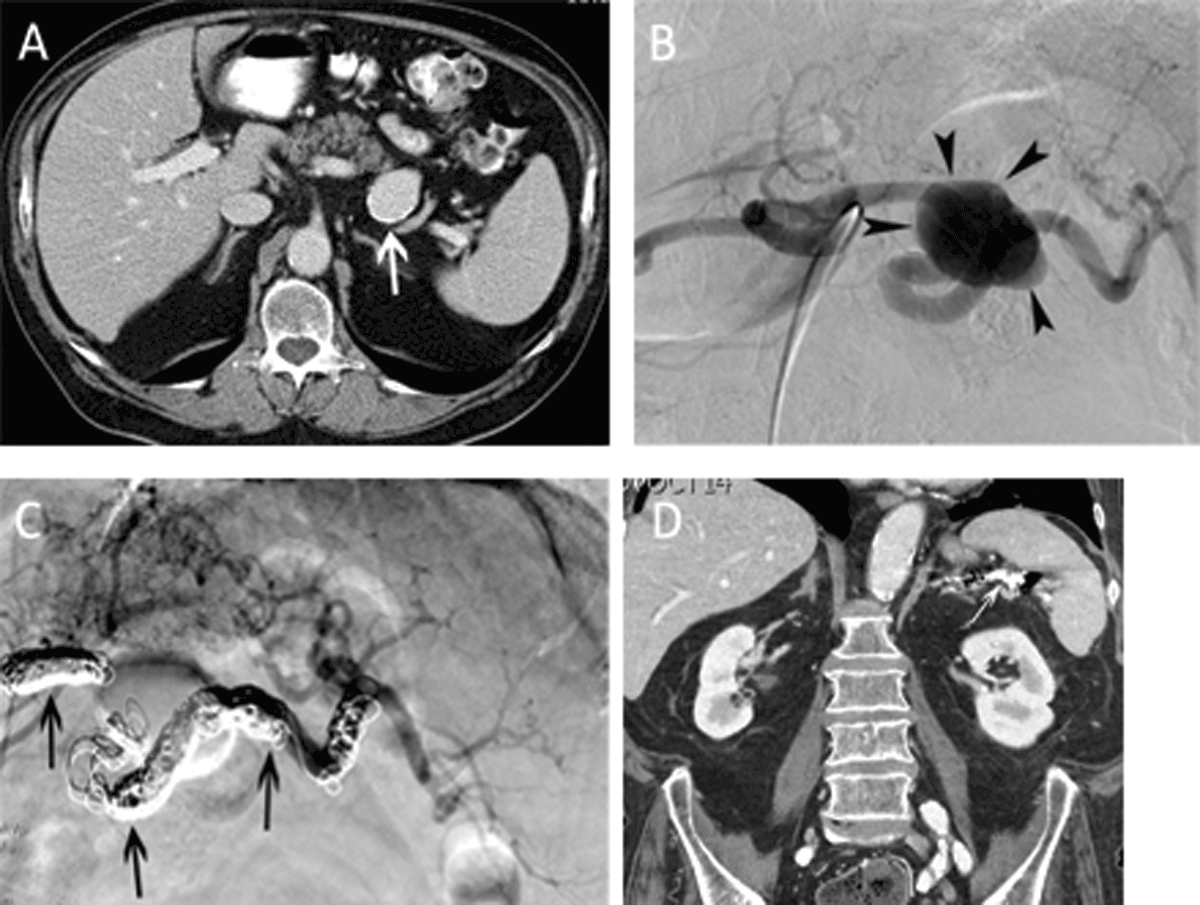

Figure 1

Main splenic artery embolization for atherosclerotic aneurysm. (A) Contrast-enhanced CT-scan in a 74-year-old man revealed an asymptomatic, atherosclerotic aneurysm (white arrow) with a maximal diameter of 37 mm. The total splenic volume was 418 ml. (B) Selective angiography of the celiac trunk confirmed the saccular aneurysm (arrowheads) in the middle third of the main splenic artery. (C) Completion angiography after coil embolization (arrows) demonstrated exclusion of the aneurysm and reinjection of the intrasplenic arteries through gastric collaterals. (D) Follow-up CT-scan 5 years after coil embolization revealed an homogeneously enhancing spleen with a total volume of 264 ml.